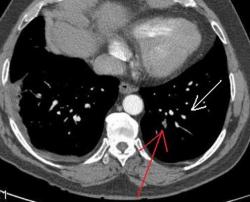

3аключение КТ что: далее цитирую "Патологические изменения в нижней доле правого лёгкого могут соответствовать остаточным явлениям перенесенной пневмонии, инфарктам лёгкого вследствие тромбоэмболии легочной артерии." это не заключение КТ по поводу ТЭЛА. Если пациент изначально направляется на КТ с подозрением на ТЭЛА, то и сьемка должан проводится по протоколу ТЭЛА (срезы 1 мм или ниже; болюс контраст; снимаем снизу вверх против тока крови). Я приведу ниже два скана разных пациентов с ТЭЛА:

скан 2: тромбоэмболия суб-сегментарных (!) веточек базальных сегментов левой нижней доли. Тромб указан красной стрелкой;нормальный сосуд белой.